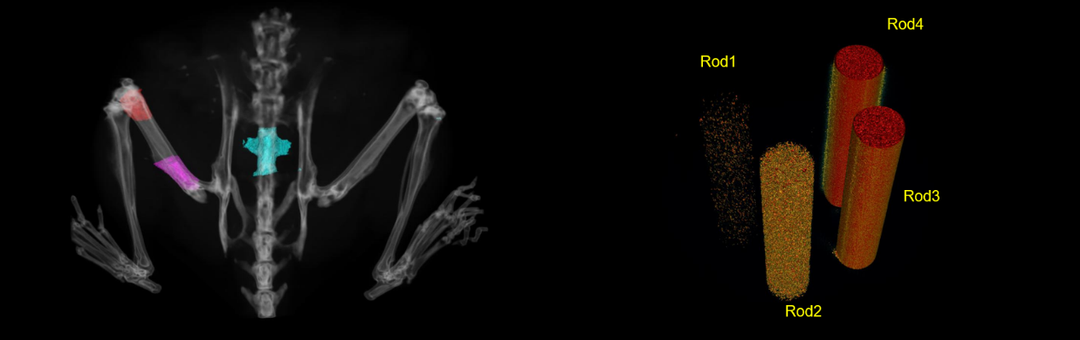

骨质疏松小鼠模型 (Ex/In vivo)-密度属性、结构性参数

卵巢切除诱导的骨质疏松模型离体检测。(a)骨质疏松模型假手术组(sham)和手术组(OVX)3D重建图像。(b)骨小梁、皮质骨结构性参数以及密度属性参数统计图。指标意义参考下方表格,综上结果模型特征明显,手术成功。

活体下,测定骨密度支持自定义区域以及长度,如红色区域股骨远端,紫色区域股骨近端及脊椎骨等。Rod1、Rod2、Rod3、Rod4分别为不同密度的羟基磷灰石。

靶向抗体药物治疗药效良好。假手术组(G3),手术组(G4),药物溶剂组(G5),药物浓度递增组(G6-G8),数据显示为平均值±SEM,并使用单因素ANOVA进行分析与G4进行比较,“in vivo BMD”与G5进行比较。